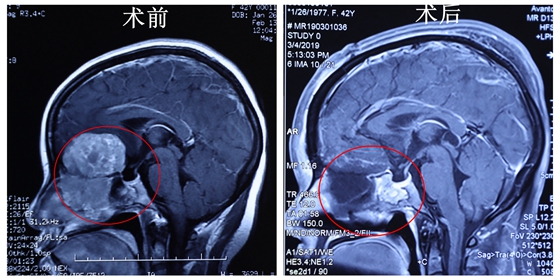

据袁贤瑞教授介绍,陈女士的肿瘤起源于颅底,一方向颅内生长,向下突破前颅底,向上往额叶底部、鞍上侵犯,压迫了患者额叶、视神经,并累及下丘脑,出现明显的占位效应,引起颅内高压,使患者视力视野出现障碍,并导致剧烈头痛;一方则向副鼻窦及鼻腔生长,瘤体侵犯了筛窦、上中鼻道,接近下鼻道,并破坏了上、中鼻甲全部粘膜及下鼻甲部分粘膜,中间突破了鼻中隔,累及对侧部分鼻粘膜,导致患者的嗅觉、呼吸障碍。

7小时的手术,袁贤瑞教授教“去”了还要“添”。他清除了颅内、前颅底、副鼻窦及鼻腔内的肿瘤后,颅内与鼻腔自然出现了一条“通道”。这条非天然的“通道”实则很危险,脑脊液可以通过它流入鼻腔,鼻腔细菌可以通过它逆行进入颅内,引发颅内感染,危及患者生命。所以切除肿瘤后还有个“重头戏”——颅底重建,把这条非自然的“通道”彻底堵死,那就需要往颅底填充脂肪。通道密封好,既保证了患者颅底的密封性和完整性,又让鼻腔恢复往日的通畅。术后,陈女士的头痛立马消失,精神状态也变好了,全家人的心情也舒畅了。